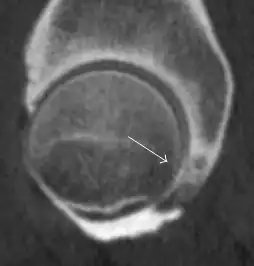

Intra-articular osseous causes of pain include several conditions: avascular necrosis (AVN), transient osteoporosis of the hip (TOH), tumors, and stress or insufficiency fractures. All these entities may present with a pattern of bone marrow edema characterized by decreased signal intensity on T1 weighted images and increased signal intensity on fluid sensitive sequences, such as fat saturated T2-weighted or STIR images. When there is no evidence of a focal lesion associated with the edema pattern, TOH is suspected. When a band of low intensity is seen inside the edematous area, the shape and length of this band become important. It is generally convex to the articular surface in the case of subchondral stress or insufficiency fractures, whereas it is concave, circumscribing all of the necrotic segment, in cases of AVN. When doubts do persist, gadolinium-enhanced MRI tends to show that the proximal portion beyond the band is enhanced in fractures but is not in AVN.[1]

MRI has been shown to have 100% sensitivity and specificity in prospective studies of occult hip fractures. These fractures were diagnosed by bone marrow edema and a low signal fracture line, mainly on T1 or T2 weighted images (Figure 10).[1]

Figure 10:

-

Stress femoral neck fracture in a young athlete barely visible in X-ray film as a sclerotic line (arrow)[1] -

In this case, Tc 99 scintigraphy shows a band of uptake[1] -

Furthermore, T1 (left) and DP fat saturated (right) weighted MR images showed the fracture line and a pattern of edema.[1]